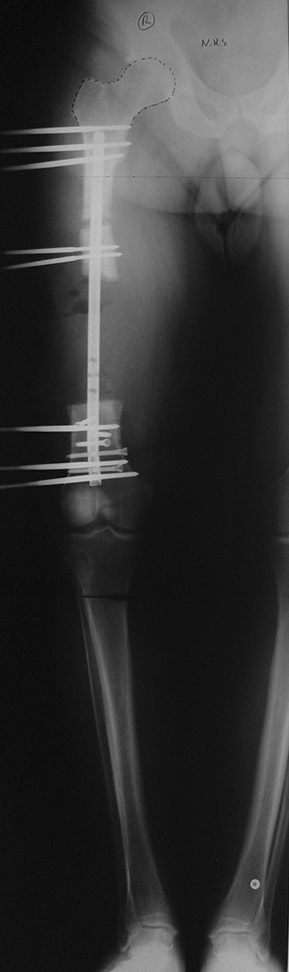

Appropriate radical debridement necessitates excision of all necrotic bone and soft tissues, and frequently causes instability at the involved extremity. The remaining bone and soft tissue defect has to be fixed and reconstructed. The distraction osteogenesis method of Ilizarov is used successfully for achievement of union, correction of the deformity, elimination of limb length inequality and reconstruction of segmental bone defects.

The duration of external fixation (external fixation index) depends on the amount of distraction required, and the extremity is prone to complications during this period. After the distraction phase is completed, the external fixator remains in place during the consolidation phase, which lasts twice as long as the distraction phase; but this period is hardly tolerated. If the external fixator is removed before sufficient consolidation is achieved, fractures, deformity and shortness will be the result. In our department, ‘lenghthening over nail’ method is used in order to decrease the external fixation index and increase patient comfort and activity level. In this method, the intramedullary nail is statically locked after the completion of the distraction phase, and external fixator is removed. The extremity is stabilized by the intramedullary nail during consolidation phase. In this way, complications due to long external fixation index or early removal of the external fixator are avoided.

Case 3